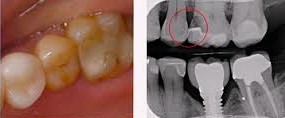

a. 충치 및 내부 이상

표면에 드러난 충치뿐만 아니라,

우식이 치아 내부의 치수 조직이나

인접치 쪽으로 확산되었는지

평가할 수 있습니다.

더불어,

브릿지, 크라운과 같은 보철로 덮인 치아의

내부에 새로운 우식이나

뿌리 염증이 나타났는지

확인할 수 있습니다.